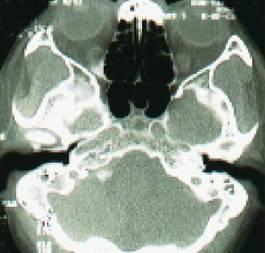

2、影像学检查:CT扫描显示窦口鼻道复合体或鼻窦粘膜病变。

• 副鼻窦X线检查,CT(冠状位、轴位)检查已常规应用。

鼻窦炎轴位CT